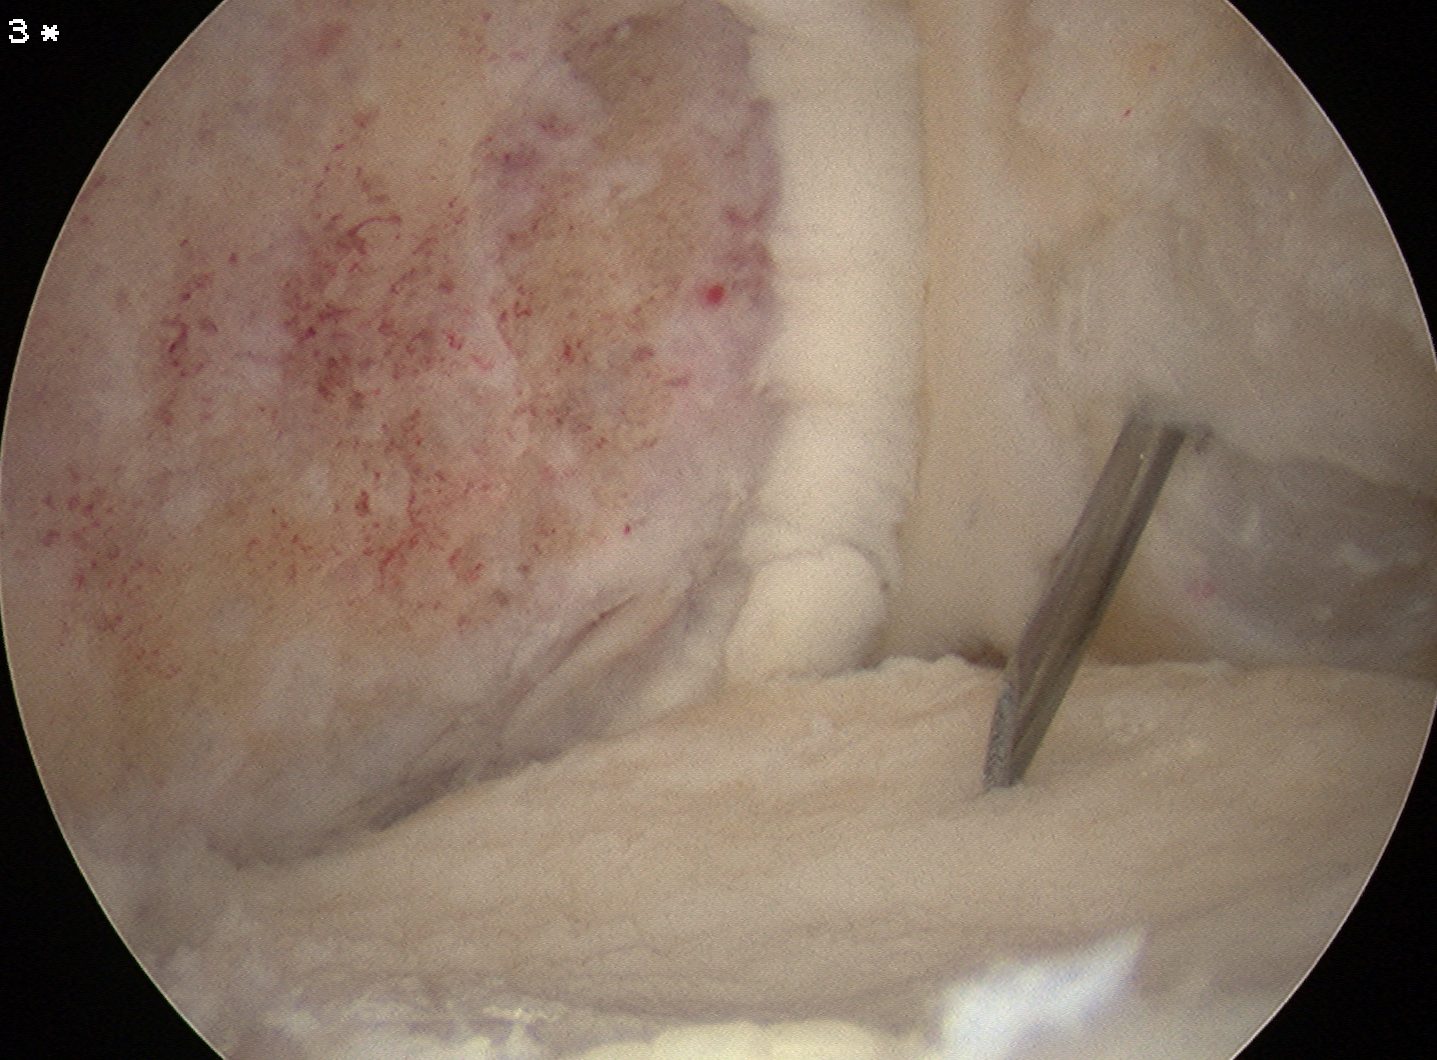

Mobilisation of fragment

Lesion carefully mobilised with scaple and probe

- left to lever open inferiorly

- want it to stay partially attached

- need to release some fibres of PCL medially

- insert spinal needle from medial knee to hold fragment open